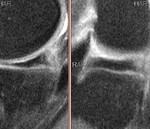

[画像診断]極めて小さな半月板断裂について 2010-06-16